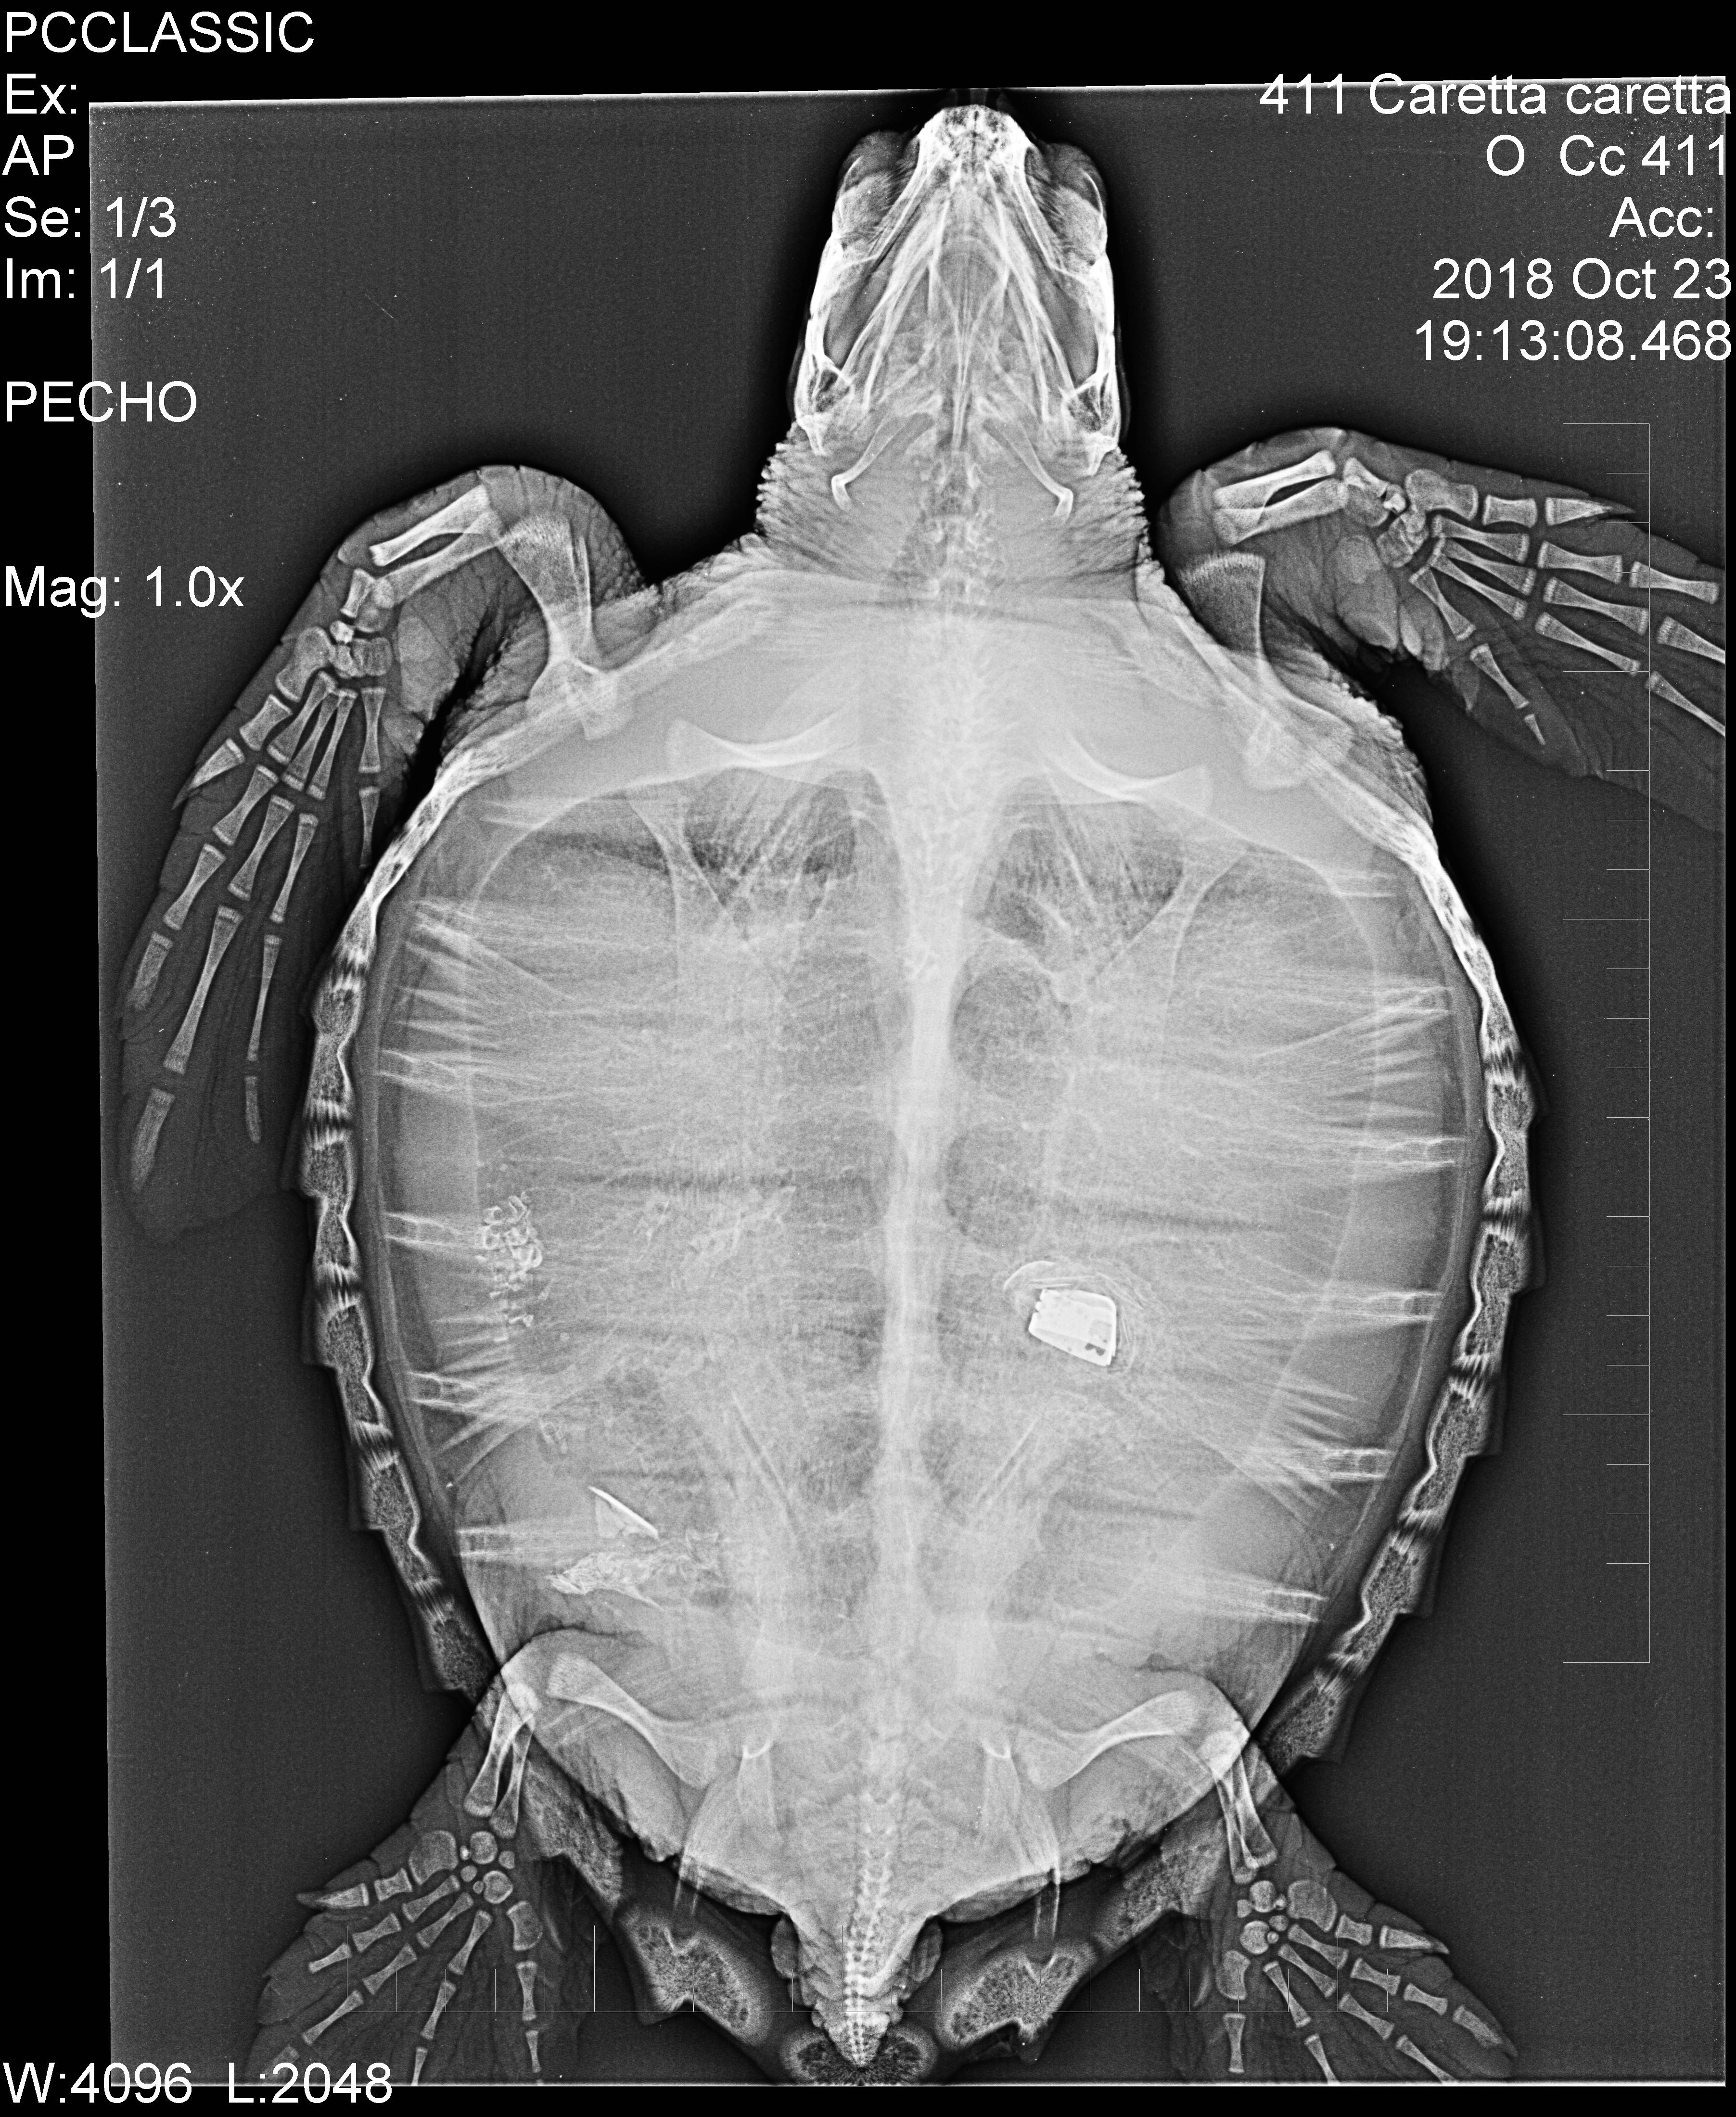

En el ARCA del Mar descubrieron que el quelonio, como tantos otros, sufría una embolia gaseosa leve por lo que fue introducida en la cámara hiperbárica para su recuperación. Pero dentro de los controles rutinarios se le hizo una radiografía y en ella se observó claramente el cabezal metálico de un mechero. Enseguida se dispararon las alarmas, pero el posterior análisis tranquilizó a los veterinarios que pensaron, y acertaron, que el animal terminaría expulsando el objeto extraño vía tracto rectal, cosa que sucedió.